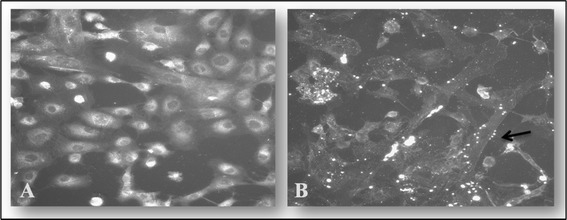

Microscopic analysis of adherent Mmm to BoLEC showed uneven distribution of Mmm on the cell surface. The adherent mycoplasmas appeared as aggregated bright fluorescent spots on the surface of the cells (Figure 1). Due to the small size of Mmm, it was not possible to visualize individual Mycoplasma cells under the conditions used.

Figure 1.

Indirect immunofluorescent staining of Mycoplasma mycoides subsp. mycoides ( Mmm ) bound to bovine lung epithelial cells (BoLEC). A shows BoLEC without Mmm stained with anti-Mmm (Afade) + anti-rabbit FITC and counter stained with DAPI. B shows BoLEC with adherent Mmm stained with anti-Mmm (Afade) + anti-rabbit FITC and counter stained without DAPI. The arrow indicates bright fluorescent patches of Mycoplasma clusters on the surface of an epithelial cell.